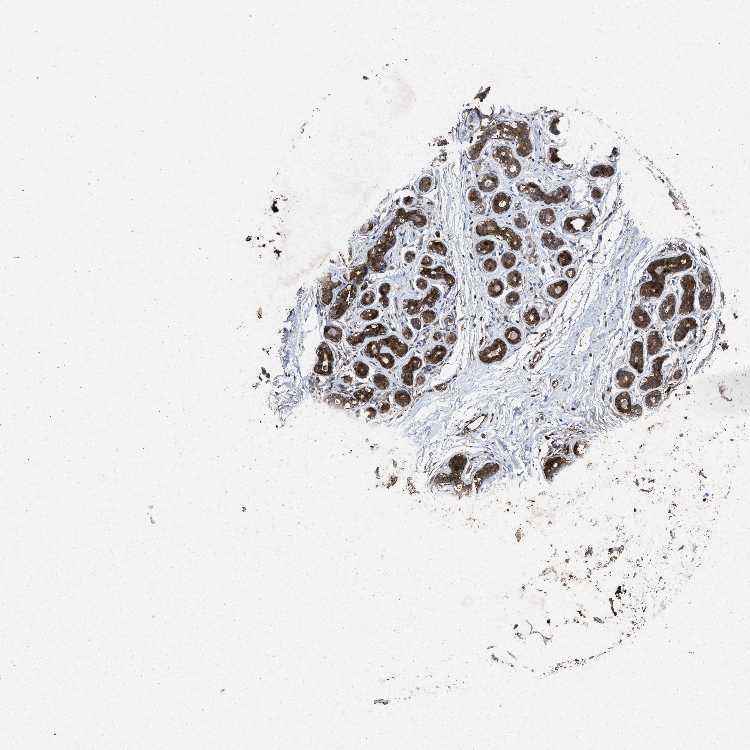

BREAST - Antibody stainingi

Antibody staining in the annotated cell types in the current human tissue is reported as not detected, low, medium, or high, based on conventional immunohistochemistry profiling in selected tissues. This score is based on the combination of the staining intensity and fraction of stained cells.

Each image is clickable and will lead to virtual microscopy that enables deeper exploration of all samples and also displays staining intensity scores, fraction scores and subcellular localization as well as patient and tissue information for each sample.

Antibody CAB022300

Adipocytes Low

Glandular cells High

Myoepithelial cells High